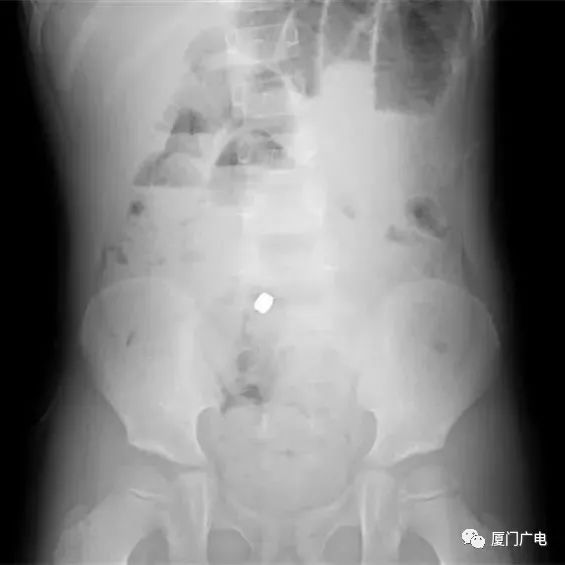

男孩尿道塞30颗磁力珠,背后原因引关注,家长需警惕“看到一条新闻,一个14岁的小男孩竟然把一串磁力珠塞进尿道。过了4个小时后,这个小男孩开始肚子痛,尿血,家长意识到严重性,赶紧带孩子去... 对大人不好意思讲,或者问出内心的想法后,得到大人不好意思的搪塞后,好奇的他们就会通过各种渠道,试用各种方法去了解自己想知道的问题,例...

震惊!男孩往尿道塞了94颗磁力珠 就医时已形成坚硬的结石外壳前不久,十三岁男孩小禾肚子疼得厉害,起初家人以为是吃坏了东西,可疼痛两天都不见缓解,还出现了血尿,家人赶紧带他来到医院,最终医生从小... 出现不明原因的反复腹痛、排尿疼痛、尿频、尿急、血尿等症状时,家长和医生需要警觉,询问“是否有异物塞入?”,一旦怀疑或确认有异物塞入...